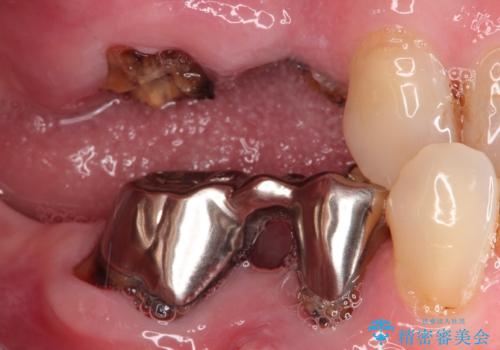

右上のかぶせ物がとれてしまい、残った根っこも虫歯になってしまっていました。

また右下の歯も虫歯と歯周病により長く使用するには難しい状態でした。